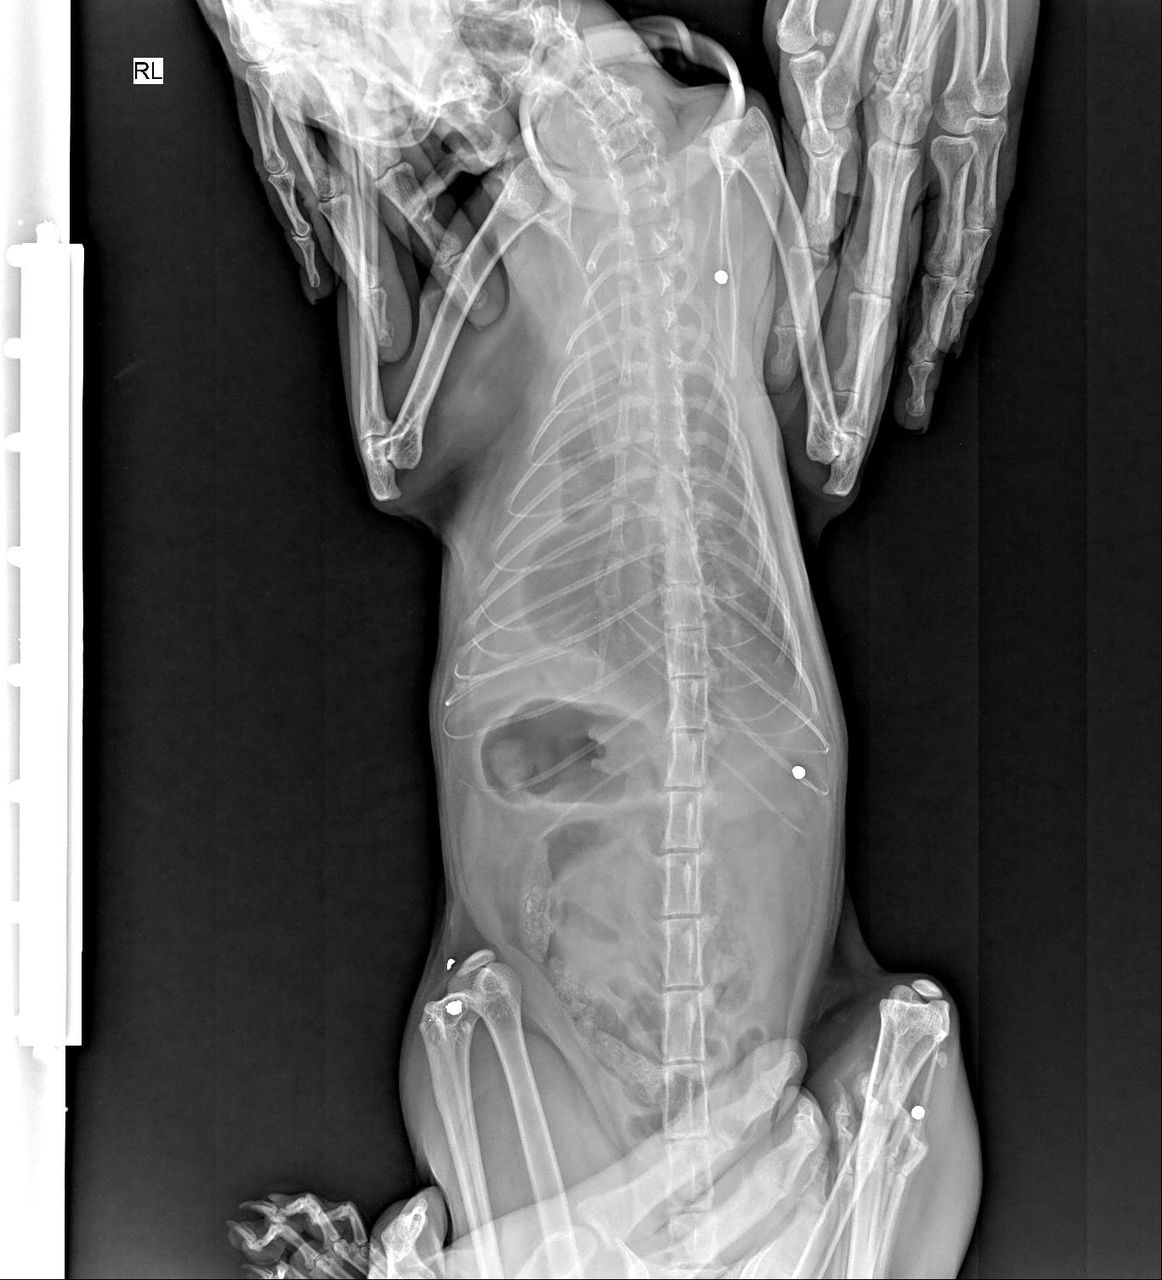

«В своей практике я довольно часто сталкивалась с подстреленными кошками. Большинство из них спасти не удалось. Некоторые до сих пор живут с пулями в теле. Это страшно — видеть, как животные страдают из-за человеческой жестокости. На фотографиях — рентгеновские снимки, на которых видны застрявшие пули. Кроме того, в уставе муниципального предприятия “Тазалык” прямо указано положение об “отстреле кошек”, а не только собак. А в текстах тендеров на проведение мероприятий по отстрелу животных в пригородных районах также упоминается отстрел кошек».